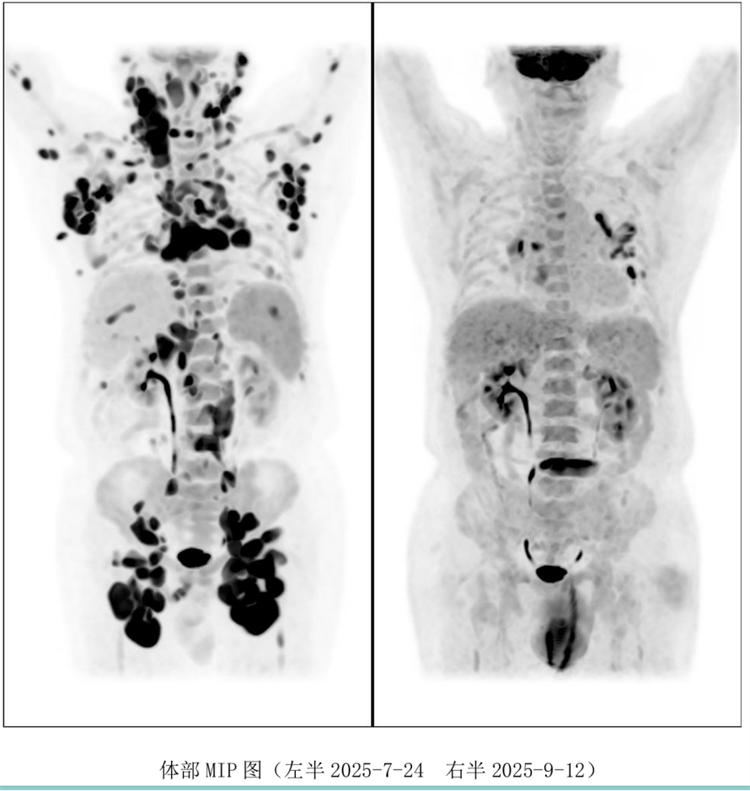

病例過(guò)程跌宕起伏,從橋接治療到靶點(diǎn)的選擇,并發(fā)癥的處理都極具代表性。張醫(yī)生詳盡分享了患者在治療過(guò)程中的挑戰(zhàn)、決策依據(jù)以及CAR-T細(xì)胞治療后的驚人緩解與轉(zhuǎn)歸,充分展示了CAR-T技術(shù)為晚期患者帶來(lái)的突破性生存希望。